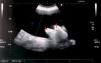

La forma de aparición de los pseudoquistes es generalmente mediante clínica abdominal muy inespecífica. La etiología más validada es la existencia de una infección concomitante del sistema de derivación del LCR, y como tal el tratamiento precisa antibioterapia y sustitución de todo o parte del sistema. Sin embargo, el pseudoquiste no necesita de un tratamiento activo, salvo casos concretos. Este manejo, presentado algorítmicamente en el presente trabajo, logra una tasa de recurrencia menor que otras opciones que, no obstante, sigue siendo importante, y se asocia además a otras complicaciones de las derivaciones relacionadas con varios factores.

The clinical presentation of pseudocysts is normally through non-specific abdominal symptoms. The most validated etiology consists on the existence of a concomitant infection of the CSF shunt system, and so, treatment needs of antibiotherapy and total or partial substitution of the system. However, the pseudocyst itself doesn’t need an active treatment, except for some specific cases. This management, algorithmically presented in the present work, achieves a lower recurrence rate than other options, but this one is still important, and is also associated with other complications of those shunts related with several other factors which need to be taken in account.